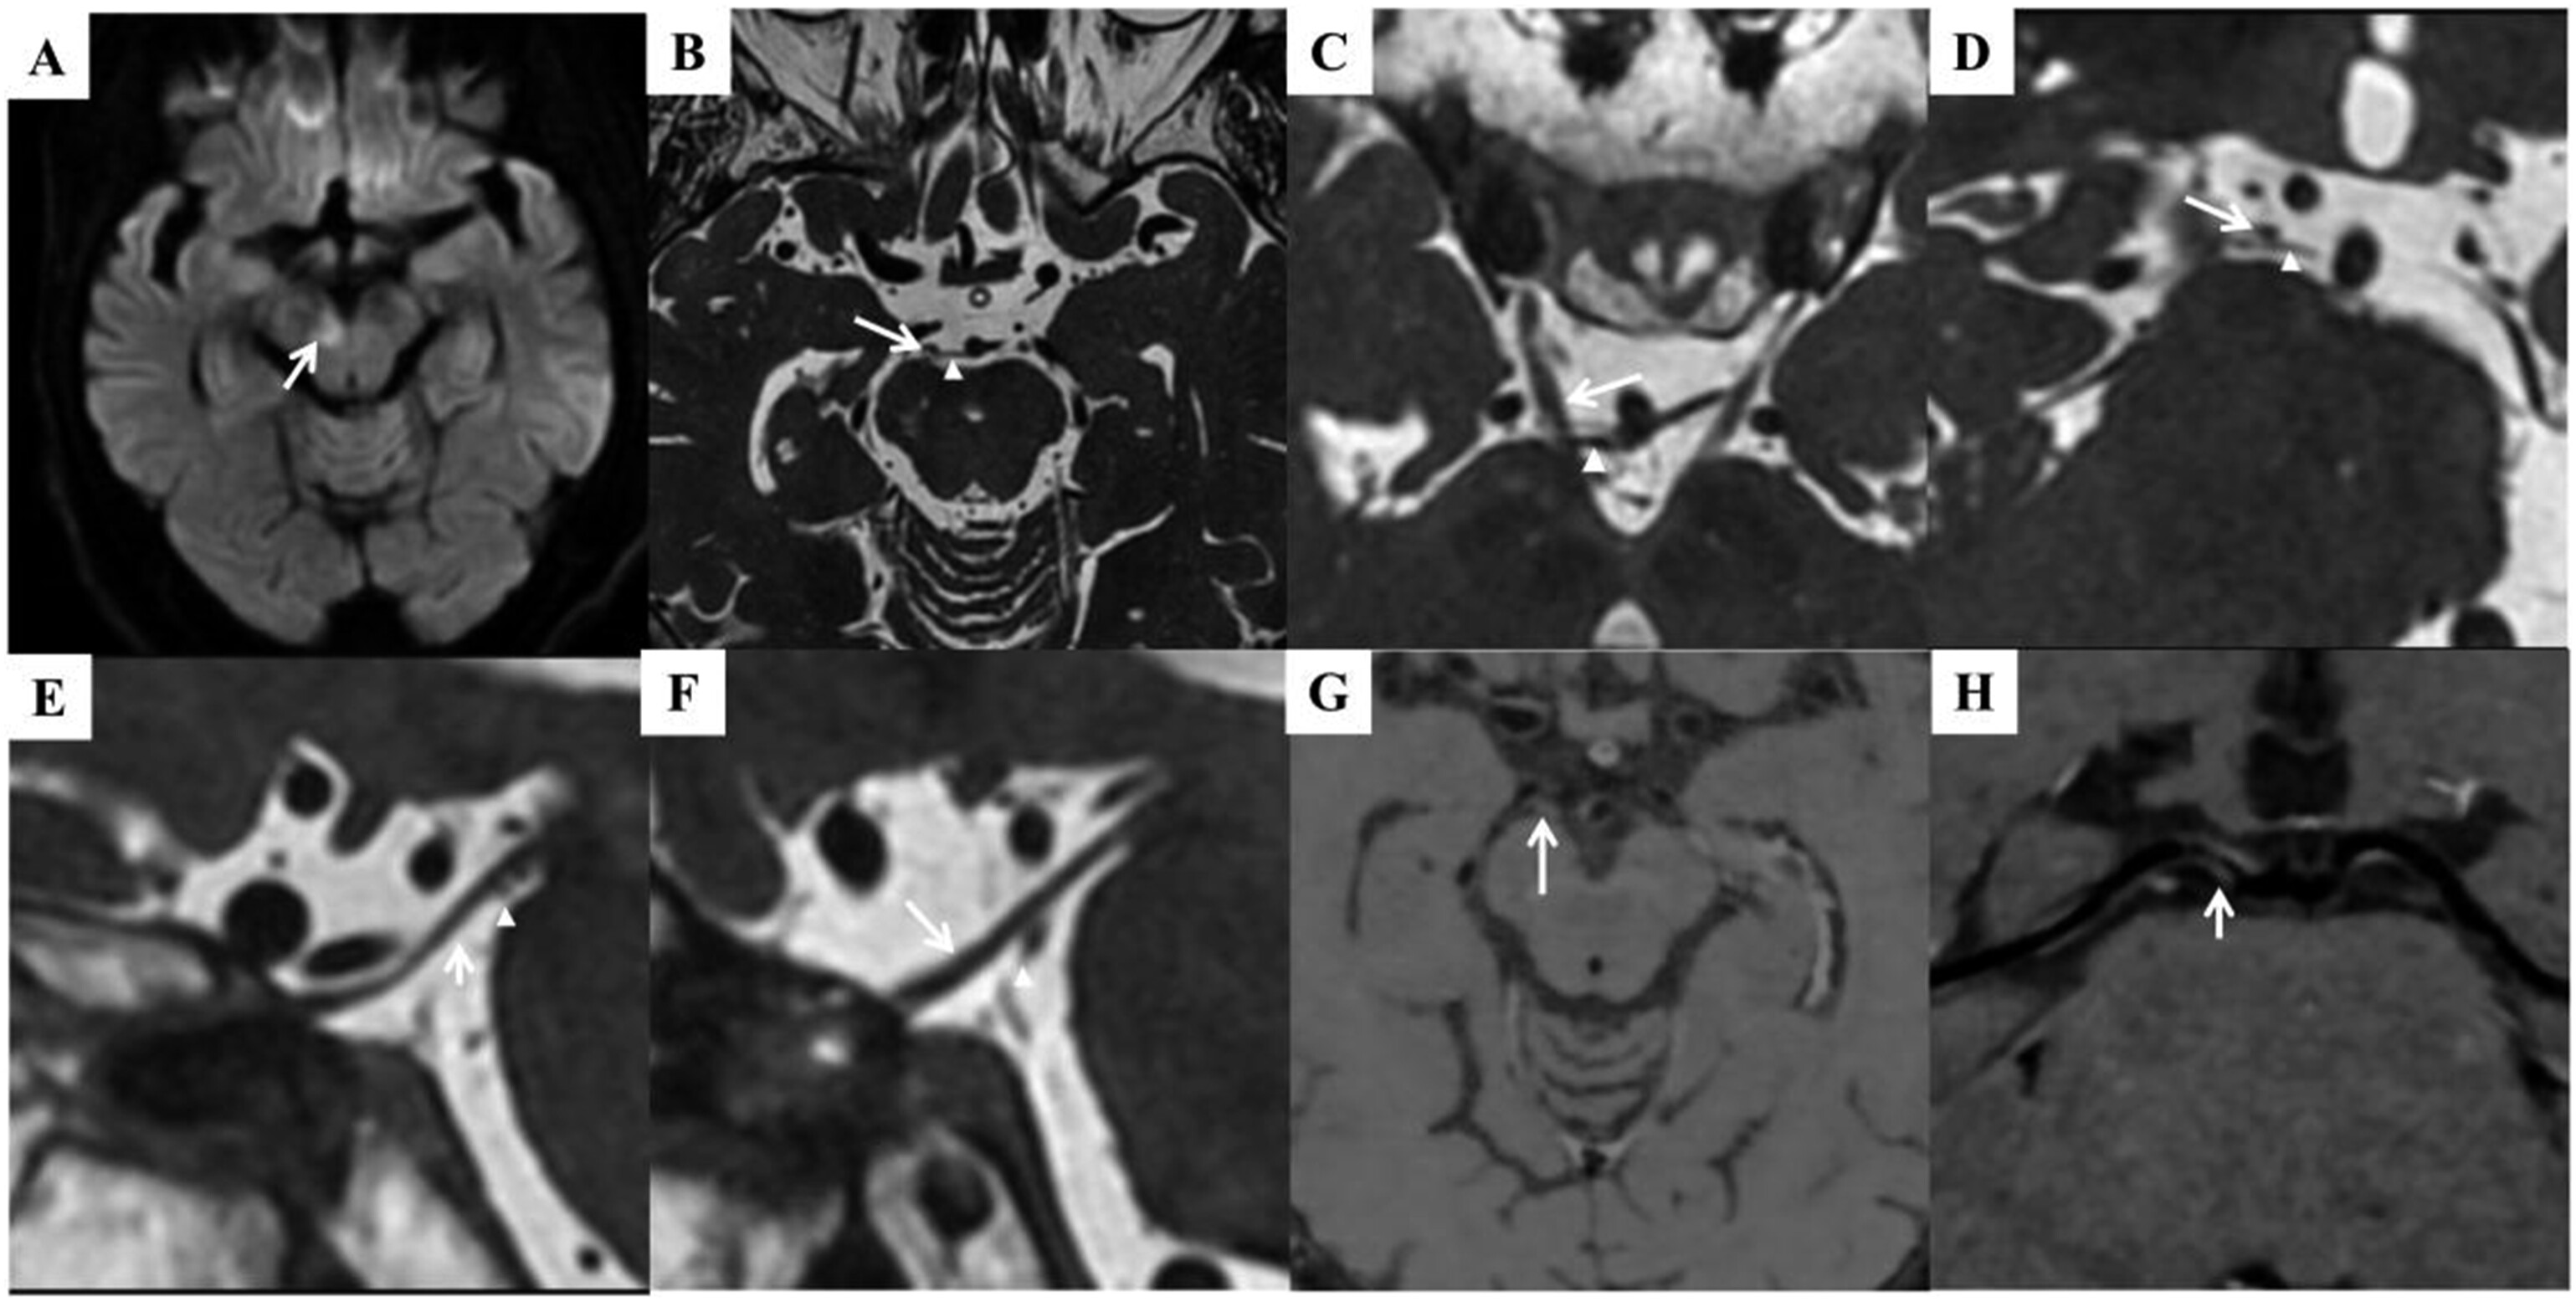

Figure 1 from Unilateral orbital pain, ptosis and binocular diplopia in three patients case Binocular Diplopia Ptosis Binocular diplopia resolves with either eye being closed and indicates ocular misalignment as an underlying problem. Diplopia (seeing double) is an ophthalmologic complaint found mainly in elder patients. It can have both ocular and neurological causes. Fluctuating binocular diplopia symptoms and signs typically worsen after exercise or when patients are tired. Binocular diplopia refers to double vision due to misalignment. Binocular Diplopia Ptosis.

(PDF) Unilateral orbital pain, ptosis and binocular diplopia in three patients case reports and Binocular Diplopia Ptosis Binocular diplopia is most commonly caused by ocular misalignment or strabismus that can be detected using simple clinical tests. Binocular diplopia refers to double vision due to misalignment of the eyes, often caused by weakness or restricted movement of the muscles surrounding the eye (i.e.,. Binocular diplopia resolves with either eye being closed and indicates ocular misalignment as an underlying. Binocular Diplopia Ptosis.

Figure 1 from Unilateral orbital pain, ptosis and binocular diplopia in three patients case Binocular Diplopia Ptosis Binocular diplopia is most commonly caused by ocular misalignment or strabismus that can be detected using simple clinical tests. Diplopia (seeing double) is an ophthalmologic complaint found mainly in elder patients. Ptosis and extraocular movement fluctuate even. Binocular diplopia occurs because the image falls outside of the fovea in 1 eye, thus triggering the perception of 2. Binocular diplopia refers. Binocular Diplopia Ptosis.